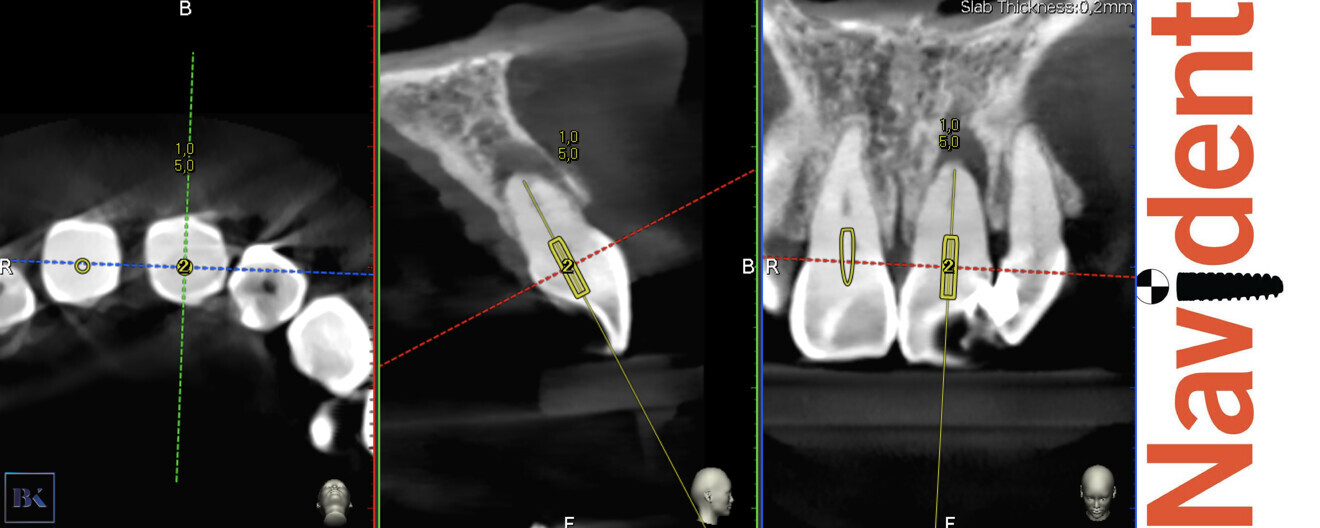

During the consultation, the CBCT scan was performed with the 9000 C 3D with a voxel size of 0.1 mm (Carestream). The CBCT scan revealed a highly calcified pulp chamber and an almost invisible trace of the root canal (Fig. 2). The patient was informed about the new, beneficial technology which can help to preserve additional tooth structure during treatment.

Figs. 2a & b: CBCT scan, sagittal (a) and coronal planes (b). Visible pulp canal obliteration and periapical lesion.

Figs. 3a–c: Planning of the virtual guide in Navident software (ClaroNav). The axis and depth of the preparation are shown.